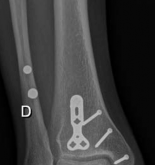

Image

Standard orthogonal radiographs (anteroposterior and lateral) are sufficient for initial diagnosis, but they routinely underestimate the complexity of partial articular fractures. A high-resolution computed tomography (CT) scan with two-dimensional multiplanar reformats (coronal and sagittal) and three-dimensional surface rendering is considered the standard of care.

CT imaging is critical for:

1. Identifying the exact location and size of the articular fragments.

2. Detecting central articular depression that is obscured by the cortical rim on plain films.

3. Mapping fracture lines extending into the diaphysis.

4. Planning the surgical approach to ensure direct access to the primary fracture line.